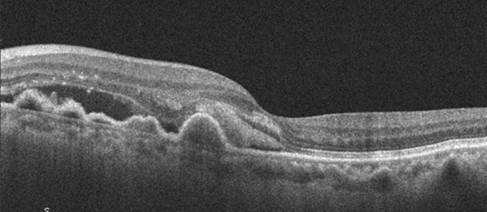

OCT macular

- Evaluación de presencia de drusas, alteraciones pigmentarias del EPR

- Detección de signos de neovascularización (exudados, hemorragias)

- Evaluación del EPR y extensión de la atrofia

- Comparación con exámenes previos para detectar progresión